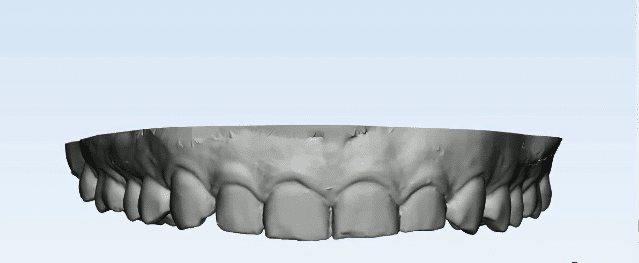

-Patient was referred to Digital dental scan to perform 2 tasks:

A-Intra-oral scanning for the whole upper arch using an intra-oral scanner.

-Soft tissue scan image & CBCT image were merged together to design a Digital crown lengthening guide.

-The digital guide has 2 level:

1-Coronal level: which is determined upon probing depths on the whole upper anterior quadrant.

2-Apical level: which is determined upon CBCT to accurately determine the needed sufficient biologic space for supracrestal fibers. “2mm”

-The guide was printed & was tried over a 3d model & also intraorally to check the coronal level is exactly like the pobing depths which were taken.